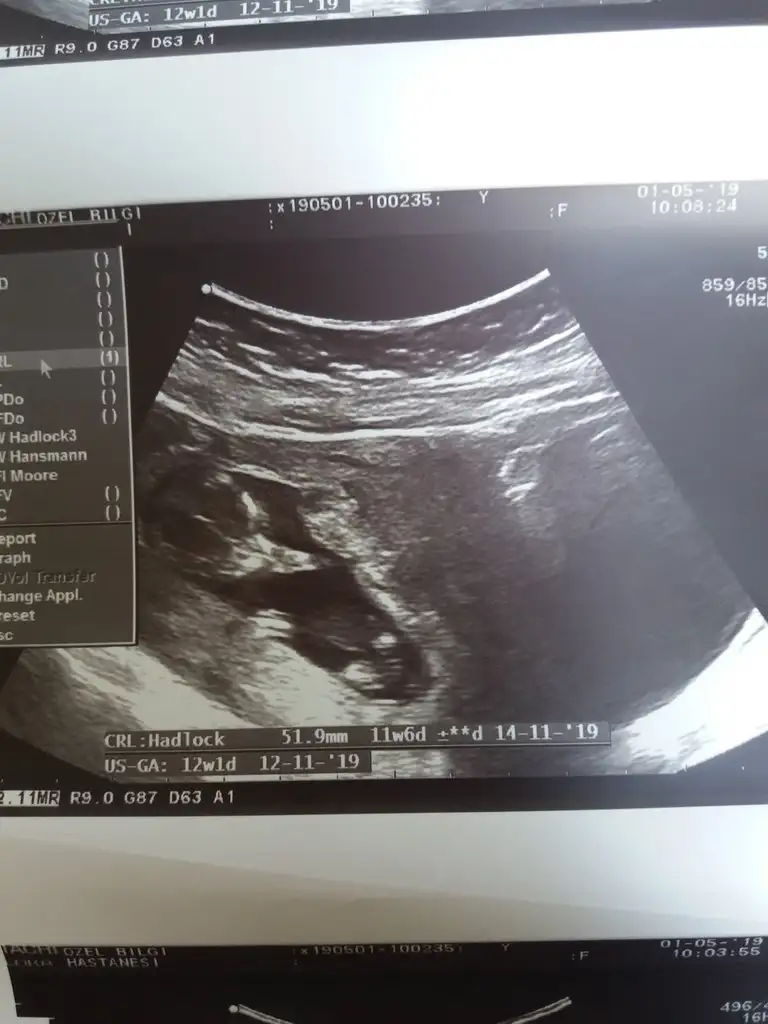

inşallah cnm sağlıkla kucağınıza alalımGünaydın kızlar, bugün 12.30da randevum var. 1 ay geçti aradan heyecan bastı. Sağlıklıdır inş herşey yolundadır. Dua edin bana da güzel haberlerle geleyim inş

hadi güzel haberlerini bekliyoruzzzAy kızlar sıramı bekliyorum kontrol icin ama heyecandan ölcem resmen